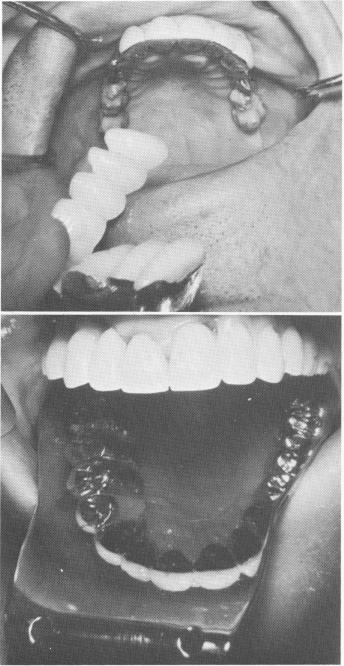

Fig. 15-78. The superstructures were tried.

Fig. 15-79. After fusing the pins with acrylic, both super-structures were cemented with hard cement over the templates.

Fig. 15-80. Implant posts were placed in both posterior edentulous areas in the mandible.

1 Endosseous pin implant superstructure try in

2 Pin implants fused with acrylic, super-structures cemented on template

3 Pin implant posts placed in posterior edentulous areas in mandible